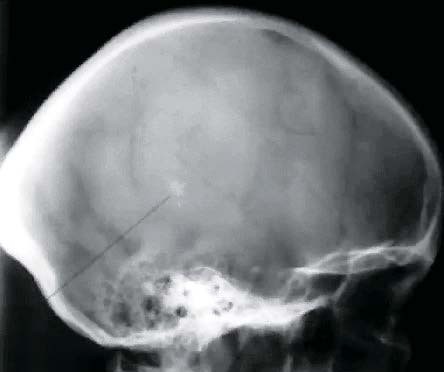

Краниография (рентгенография черепа).

Обнаруживается усиление сосудистого рисунка, расширение диплоических вен, венозных выпускников (см. рис. 2).

Рисунок 2. Обзорная рентгенограмма черепа (краниограмма). Видны расширенные диплоические каналы (признак венозно-ликворной внутричерепной гипертензии).

Сейчас редко применяют краниографию, когда есть возможность проведения КТ, но даже обычная обзорная рентгенограмма весьма информативна.